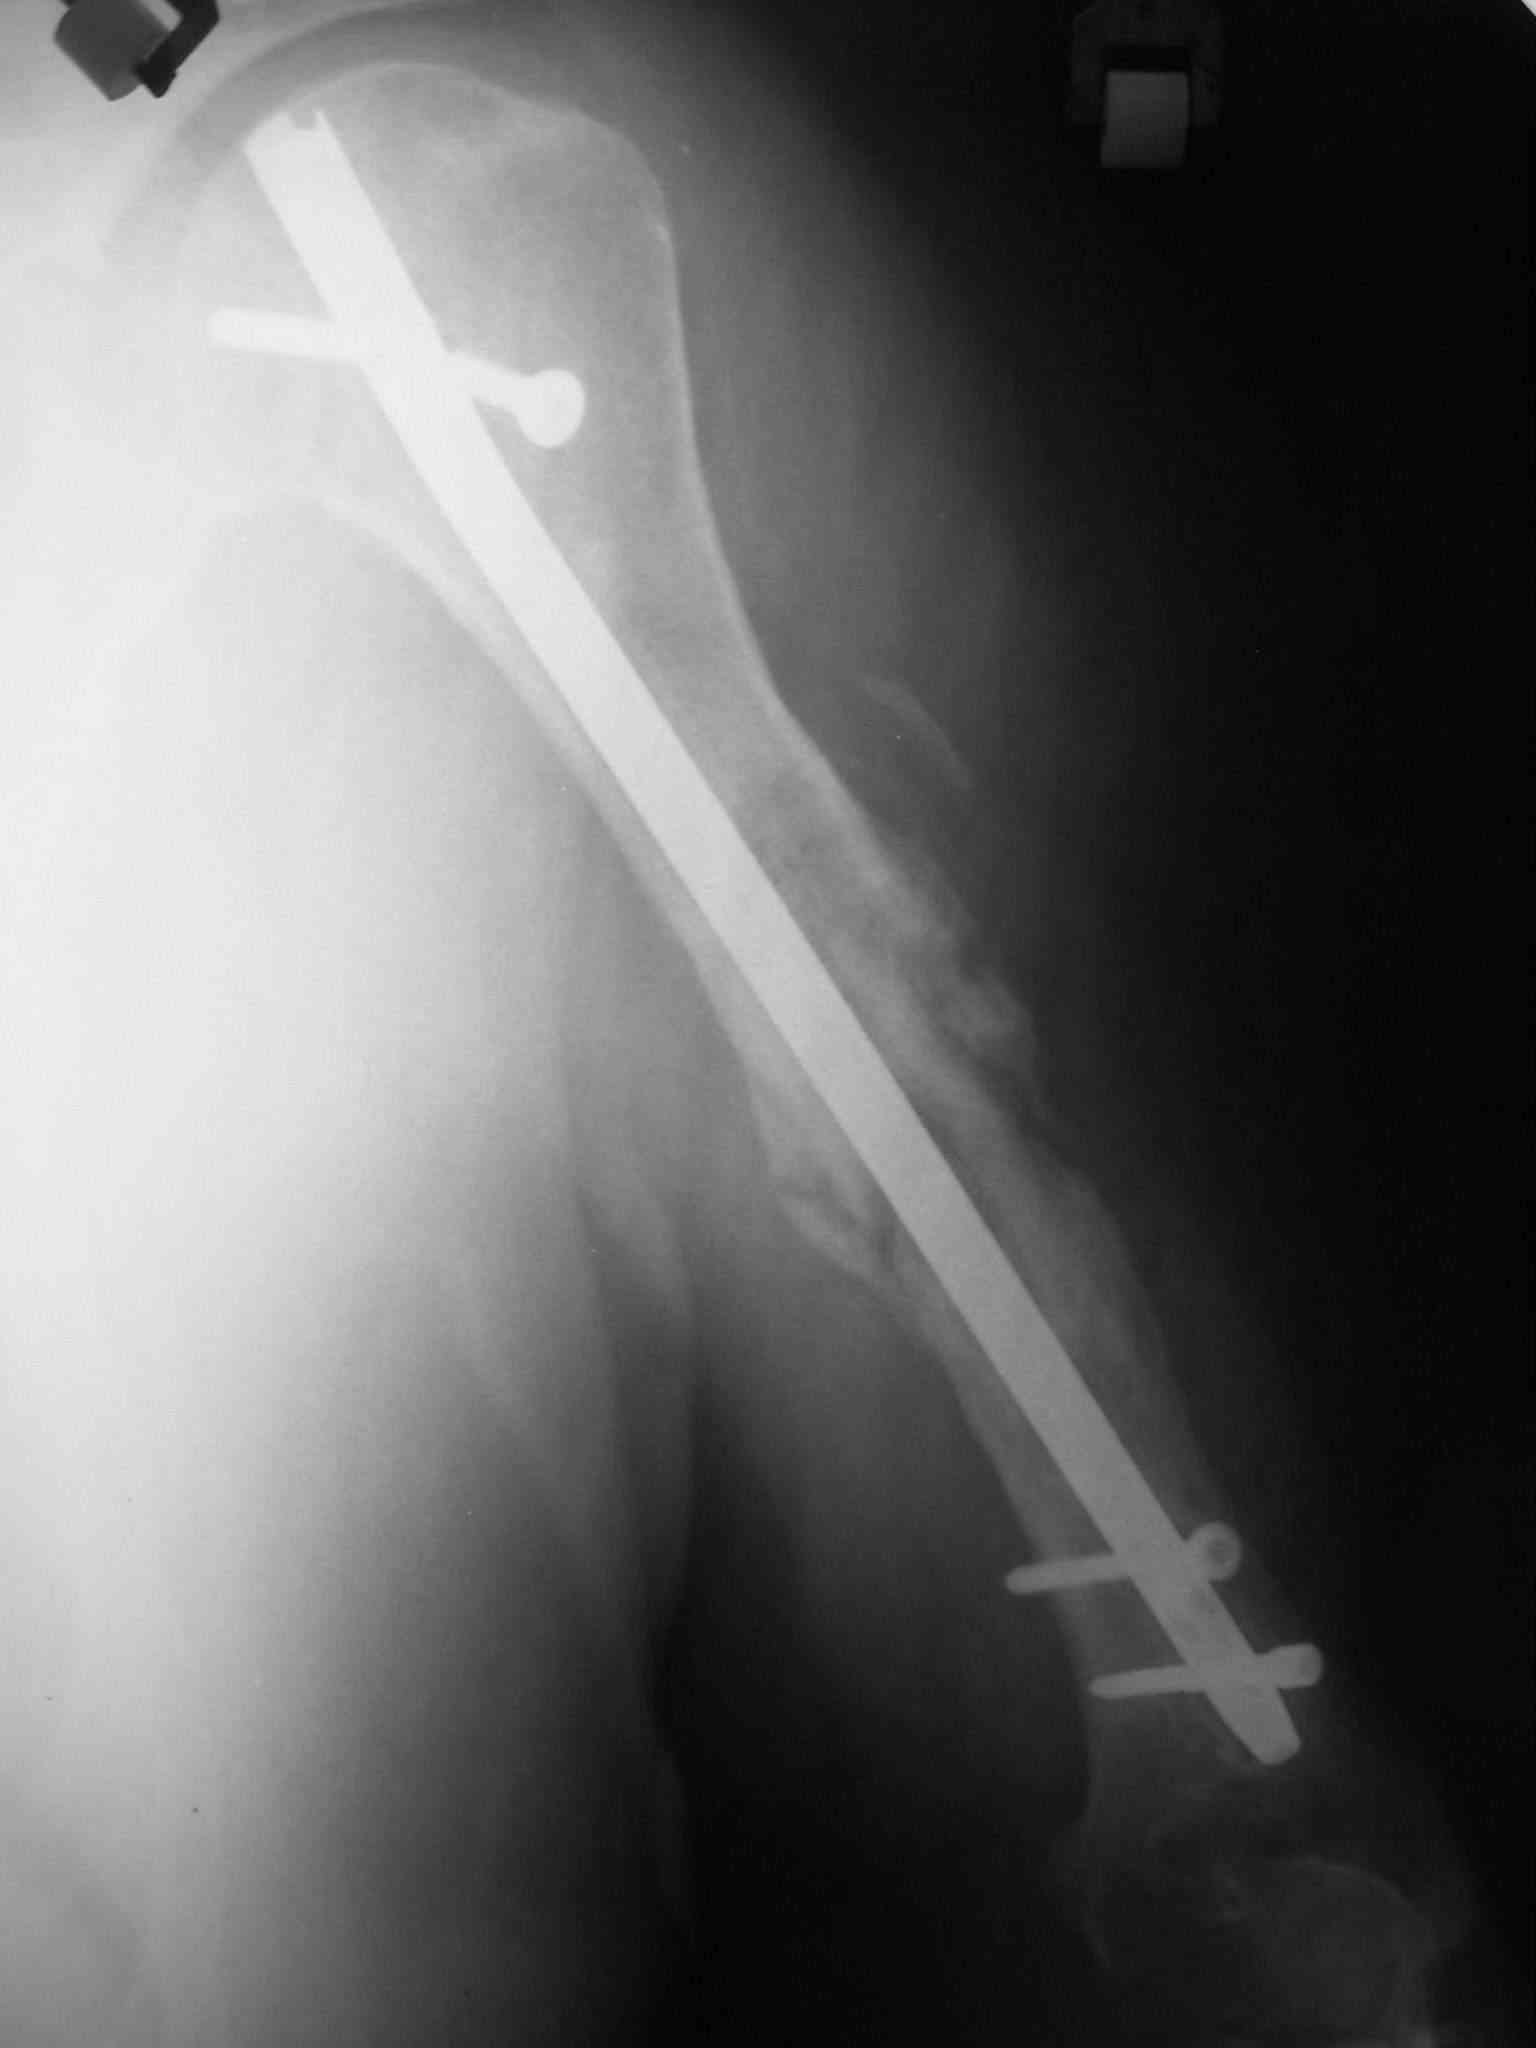

Re: Несросшийся перелом диафиза

На Вашу ситуационную задачу: у нас был аналогичный случай (у пациента Д. за три года было девять ранее перенесенных операци: штифт Богданова с гипсом-пластина-нагноение- аппараты-лечение гнойных ран и остеомиелита - опять dcp пластина-разрушение и миграция пластины....) -

БИОС делали открыто, с декортикацией, частичным торцеванием и костной аутопластикой. Вариант БИОС - компрессирующий). Насчет компрессирующего варианта БИОС потом пожалели - проксимальный блокируемый винт сломался через год, надо было делать стабильный вариант.